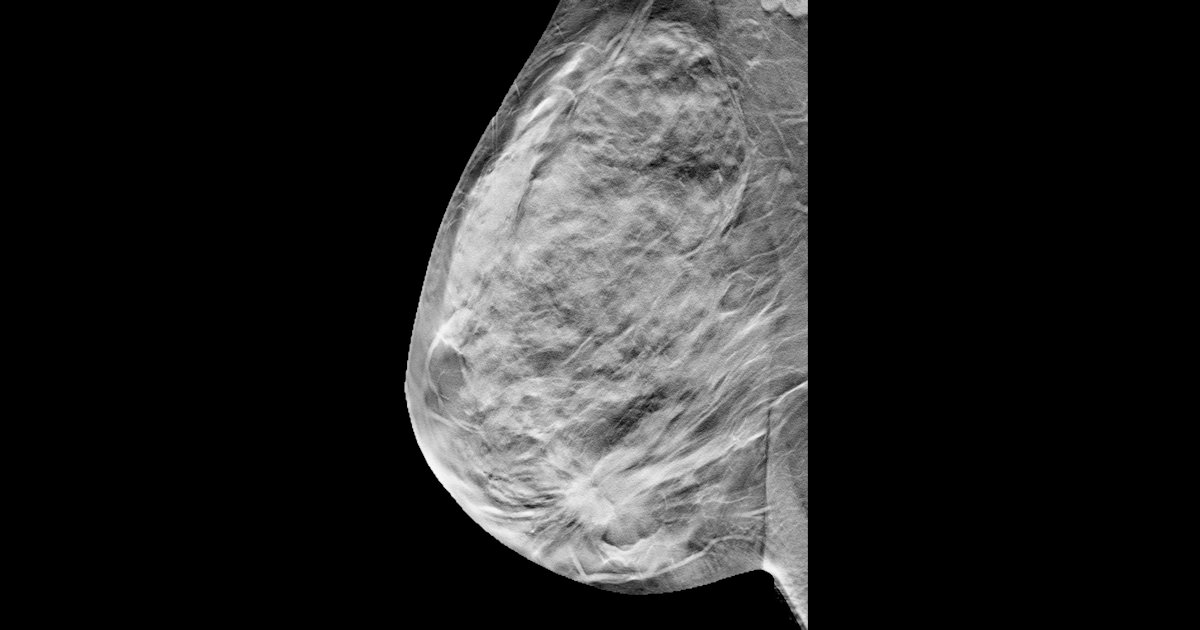

The required relative reduction in breast cancer mortality for DBT-screening to be cost-effective compared to DM-screening, for the same price as DM, DM price + €10, and DM price + €20, at willingness-to-pay thresholds ranging from €10,000 to €50,000/QALY. All figures courtesy of Adam Fridhammar et al and EJR.

In the team’s analysis, at a calculated willingness-to-pay of between €10,000 and €50,000 (with a cost of exam at a range of €51 to €71), the required relative breast cancer mortality reduction range for cost-effectiveness was from 3.6% to 10.1%, they wrote.